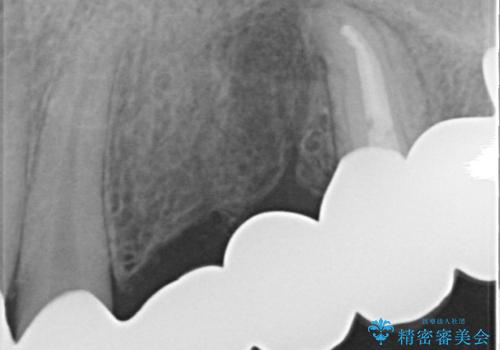

- 歯がない左側でものが咬めず、右側で咬むと歯が痛むので診て欲しいといらっしゃった方の症例です。

根尖病変が認められる歯は再根管治療を行い、歯根が破折していた左上4は抜歯しました。

インプラントは希望されなかったため、左側は1番から7番のロングスパンブリッジによる補綴を行いました。